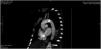

A 40-year-old woman with no relevant medical history was admitted to the ICU due to cardiogenic shock with severe systolic dysfunction and generalized hypocontractility evidenced by transthoracic echocardiography (TTE). Invasive monitoring was attempted using a thermodilution system, with great difficulty in securing ultrasound-guided access to both femoral arteries. A significant pressure gradient between the upper and lower extremities was observed. With a strong suspicion of aortic disease, a guided CT angiography study was requested, which revealed an extensive calcified atheroma plaque in the aortic arch (Fig. 1), with important obstruction in the sagittal plane reconstruction (Fig. 2). Repeat TTE was performed due to the strong suspicion of coarctation, recording a maximum systolic gradient in the descending thoracic aorta of 89 mmHg, which confirmed the disorder (Fig. 3). An endovascular approach was adopted to place a thoracic endoprosthesis supported by an intra-prosthetic steel stent. The subsequent course proved favorable, with a gradual return of ventricular function to normal levels, leaving a residual gradient of 32 mmHg.